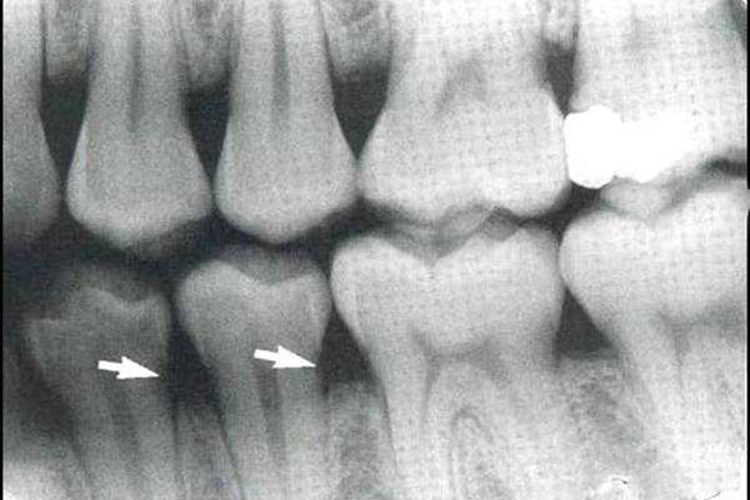

小牙片根据釉质、牙本质、牙骨质、牙髓等牙组织的密度不同,颜色表现也有所差异。由于釉质和牙本质密度较高,而牙骨质和牙髓密度较低,因此一般小牙片正常表现为外层有发白透亮度较高的牙外形,中间有1-2条根状直线阴影。

而对于牙支持组织,骨小梁为致密的薄层骨板交织构成,其间为投射的骨髓腔,牙硬板为包绕牙根的连续不断的密度高线条状影像,牙周膜则表现为密度低的线条状影像,宽度均匀一致。

如果小牙片在牙组织中显示出边界不清、密度降低的透射影,或者是边界清晰的小团骨质破坏密度甚低的透射区,密度不均匀,甚至牙硬板的包绕牙根连续不断的线条状影像消失,均属于异常情况。临床由于部分影像学变化不明显,非专业人员不容易辨认,因此建议由专业的牙科医生对小牙片进行判断。